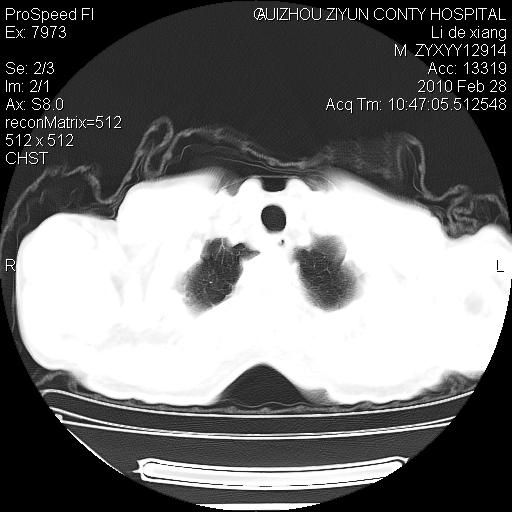

标题: CT24776:男 71Y 咳嗽咳痰胸痛两月,伴声音嘶哑。 [打印本页]

标题: CT24776:男 71Y 咳嗽咳痰胸痛两月,伴声音嘶哑。

左侧中央型肺癌伴左肺上叶阻塞性肺炎及节段性不张可能性大,建议纤支镜检查!

左侧中央型肺癌伴左肺上叶阻塞性肺炎及节段性不张可能性大,建议纤支镜检查!纵隔淋巴结转移.

左侧中央型肺癌伴左肺上叶阻塞性肺炎及纵隔淋巴结转移。

左肺门部肿块,伴左上肺斑块影,周边模糊,支持左肺中央型肺癌伴节段性不张及阻塞性肺炎,结合支气管镜检查。

左上叶支气管狭窄,阻塞性病变,肺门肿块,纵隔及肺门淋巴结增大,中央性肺癌

左肺中央型肺癌并阻塞性改变、纵膈 淋巴结转移

左侧中央型肺癌伴左肺上叶阻塞性肺炎及纵隔淋巴结转移

支持 左肺中央型肺癌伴左肺上叶阻塞性肺炎,纵隔淋巴结转移。